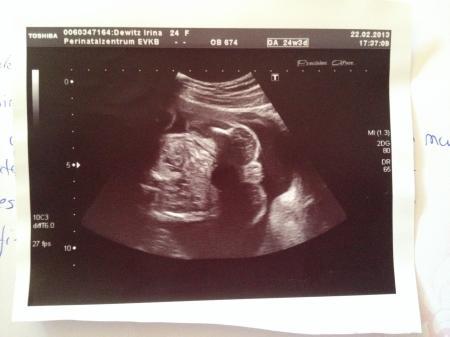

Antwort auf Beitrag von liebe1415

Huhu, Bei uns hieß es erst Mädchen (lag aber auch doof bei dem 2. Screening in der 21. SSW). Bei der Feindiagnostik in der 22. SSW war es dann ein Junge. Anbei das Beweisfoto. Ich gehe mal davon aus, dass es jetzt dabei bleibt ;-).

Bild zu